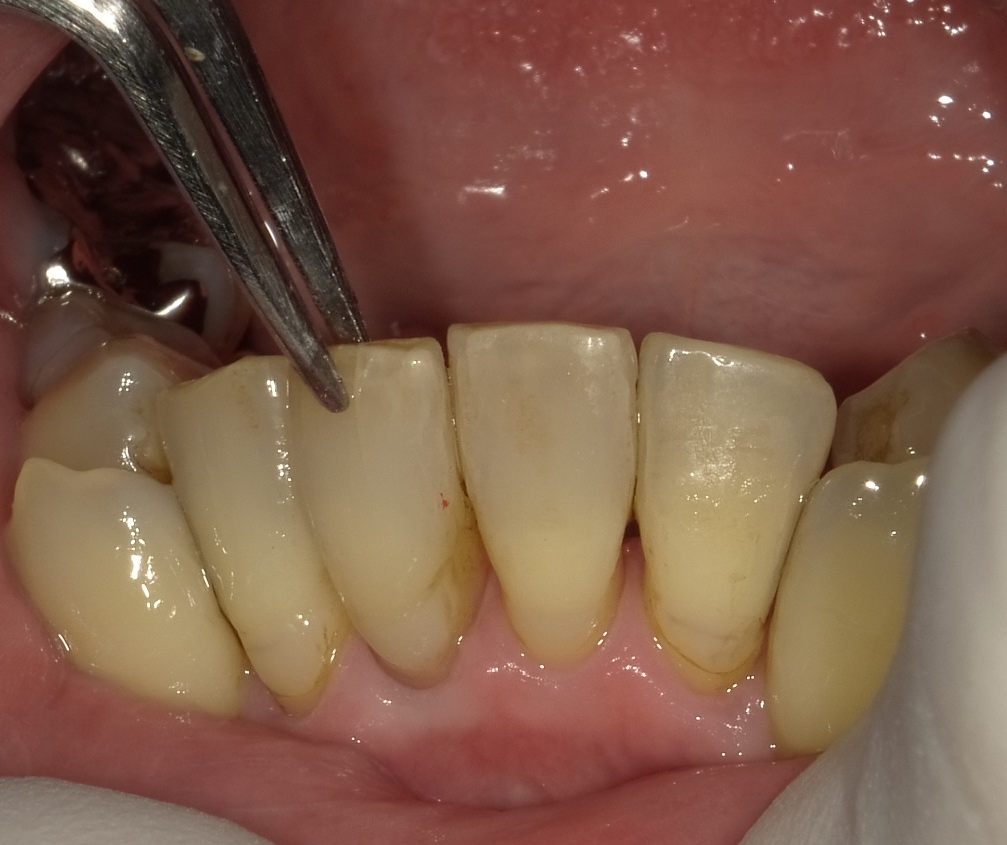

画像は下の前歯をぶつけられたとのことでピンセットで

持っている歯が外傷を受けた歯です。少しグラつきが

認められます。